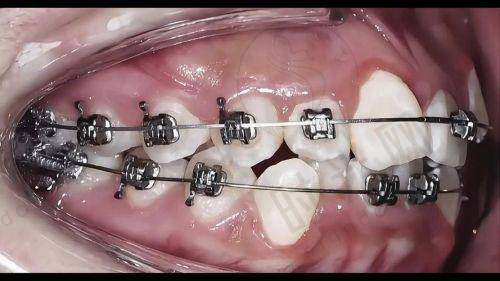

特别多人觉得去口腔医院看牙,治疗完马上就能修复正常。比如补牙后就能随便吃东西,矫正牙齿特别快就能变整齐。但实际上,补牙后牙齿可能还会有轻微不适,需要一段时间适应;牙齿矫正更是一个长期的过程,一般需要1 - 2年甚至更久。以北京牙元素口腔医院的矫正实例来看,大部分患者在佩戴矫正器3 - 6个月后才会看到明显的牙齿移动变化。

医院引入的数字化口腔扫描、3D打印等技术,也能应用到儿童口腔治疗中。对于儿童牙齿矫正,能更精细地制定治疗方案,减少治疗时间和痛苦。

张女士的女儿牙齿排列不整齐,她带女儿来到北京牙元素口腔医院。医生为孩子进行了详细检查,制定了牙齿矫正方案。在治疗过程中,医生和护士都特别有耐心,孩子也特别配合。经过一段时间的矫正,孩子的牙齿逐渐变得整齐,张女士对治疗成效非常满意。